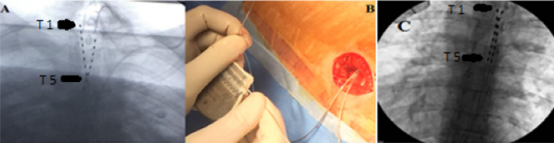

电极植入